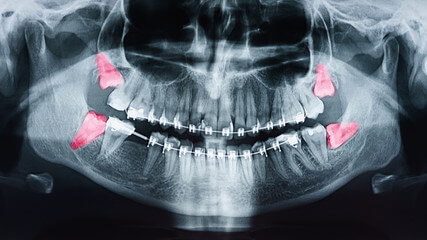

사랑니는 다른 치아에 비해 크기와 모양이 매우 다양합니다. 사랑니는 똑바로 나오지 않고 기울어져 있거나 누워있는 경우 잇몸에 묻혀 있는 부분이 많습니다.

이 때문에 음식물 찌꺼기가 잇몸과 사랑니 사이에 끼기 쉽고 칫솔이 사랑니에 잘 닿지 않아 썩는 경우가 많고 제대로 청소하지 않으면 세균이 번식하고 염증이 생기기 쉬운 상태가 됩니다.

잇몸이 부어 오르거나 아플 때 감염이 느껴지고 위턱에 있는 사랑니가 부은 잇몸을 씹으면 더 불편 해집니다. 충치는 사랑니와 사랑니 앞 치아의 뒷면에도 형성될 수 있습니다. 이러한 충치는 종종 과소 검사되며 치통이 있을 때 가장 자주 발견됩니다. 심하면 양쪽 치아를 모두 뽑아야 하는 경우도 있습니다.

사랑니 주변에 염증이 생기면 잇몸이 붓고 볼이 붓고 침이나 음식을 삼키기 어려워지며 두통이 생깁니다. 목이나 턱뼈 안쪽으로 퍼지는 경우가 많아 입을 벌리기 어렵고 때로는 입원이 필요할 정도로 심한 사람들이 많습니다.